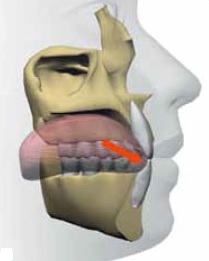

舌体は上あごの口蓋に軽く吸い付いて挙上しているのが正常な状態です。もちろん上下唇は閉じています。

舌が挙上している状態では口呼吸ができません。つまり舌が持ち上がっていることは鼻呼吸するための必要条件なのです。

ところが舌小帯が短かったりして舌の挙上が常時妨げられている場合、舌はほとんど動かないために下アゴの歯列内に収まったままの状態で、歯の痕がつくだけでなく舌本来の機能をほとんど果たしていません。